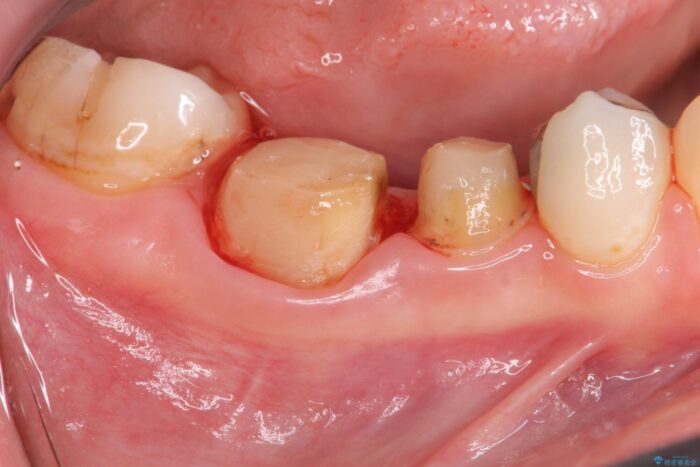

装着されていた清掃性の悪い銀歯を外すと、銀歯の下で歯ぐきよりも深い虫歯が再発していました。

虫歯を丁寧に除去し、歯周外科を用いて周囲の歯ぐきの炎症を除去します。その後、清掃性の高い精密なセラミック治療をおこなっていきます。